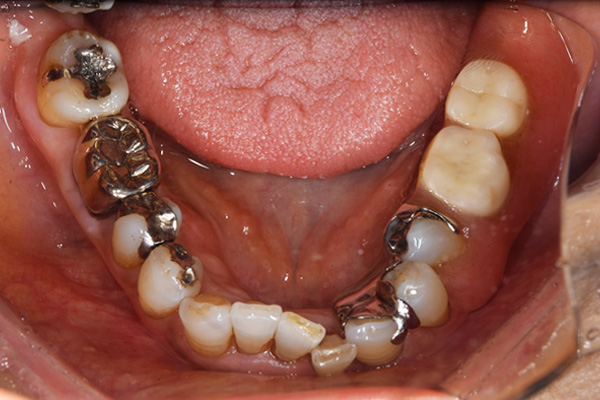

ケース1(自費の部分入れ歯)

前歯が折れて当院にいらっしゃいました。 過去に下の入れ歯を作ったが、合わなくなってずっと入れ歯をいれていらっしゃらない患者様でした。 これは奥歯で噛むことができないため、前歯で噛むことを繰り返したために、負担に耐えられなくなった前歯が折れてかぶせ物ごと 外れてしまったのだと考えられます。 痛くない、違和感の少ない、下の入れ歯を作ることがこの方のゴールであると考えられました。

シリコンで精密な型取りを行いました。

噛み合わせチェックです。 奥歯でしっかりものが噛める様に高さを決めていきました。

金属を使用して、薄く違和感が少ない入れ歯が完成しました。 また、見た目にも気を使い、バネが見えにくい様な構造にしました。

入れ歯をお口の中にいれた状態です。前歯もMTMといって、歯を少し引っ張り出す処置を行なったことで、しっかり残せて、またかぶせ物をしました。

年齢 70歳・女性

主訴 前歯が取れた

治療期間 8ヶ月

治療費 .MTM:110,000円

.ファイバーコア:16,500円

.E-maxクラウン:110,000円

.義歯:660,000円

治療方針 長年使ってきた義歯の人工歯が磨耗し、臼歯部での咬合がすくなくなり、前歯部での接触が強くなったことで生じた前歯の破折なので、義歯も作り変える必要がある。

治療内容 前歯部MTMと同時に審美面の回復。

MTM中に義歯の作成も同時に行う。

最終的に義歯と前歯のクラウンを同時にいれる。

義歯は下顎で、しっかり噛めること、違和感の少ないものという希望があったため、なるべく入れ歯を薄く作成するために金属をしようした義歯とした。

また、見た目もあまり義歯が目立たない様に、バネの部分を見えにくいように作成した。

特記事項 歯にもともと入っていた金属の種類によっては、歯自体の変色を治療で変えられないこともある。 義歯は作ってから痛みがでることがありますが、それは調整を行うことで痛くなくすることができます。